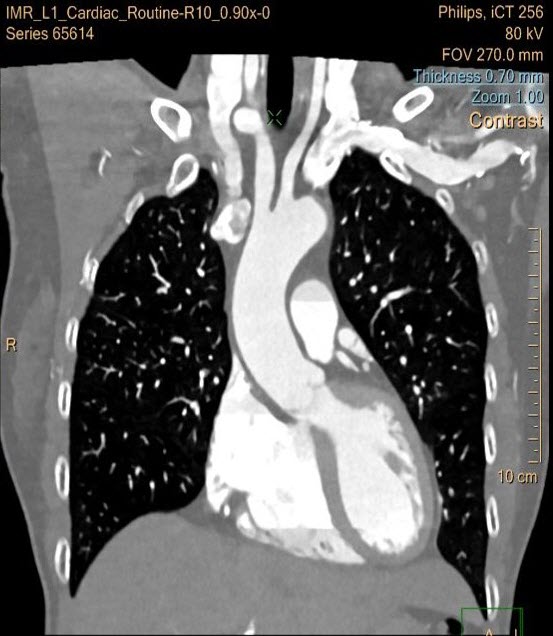

Chungang University Hospital “PCTA (prospective coronary CTA) showed significantly improved subjective and objective image quality parameters for coronary vessels with IMR compared to FBP and iDose⁴. PCTA using 80KVp and IMR could be applicable in routine clinical setting with less radiation dose.”

South Korea

Dr. Jae Suung Seo, Dr. Sung Bin Park & Team